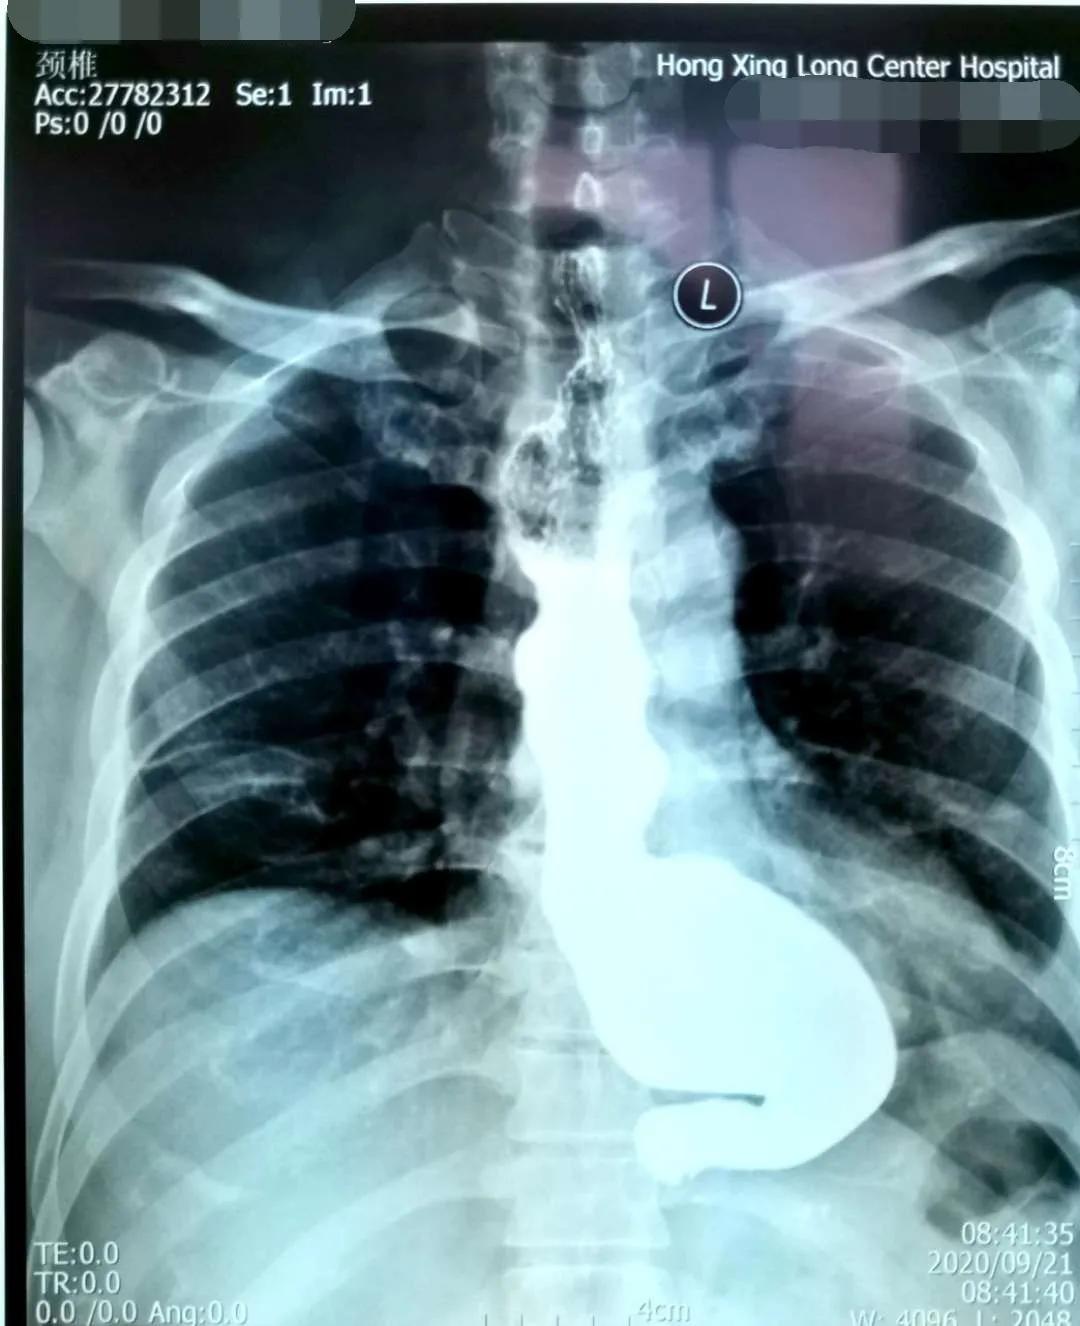

简要病史:患者吕某,男,54岁,因吞咽困难10年余,不能进固体食物,并伴有胸痛,近半年仅能进食流食,来我院诊治。

贲门失弛缓症又称贲门痉挛、巨食管,是由于食管神经肌肉功能障碍所致的疾病,临床表现为咽下困难,食物反流和下端胸骨不适,以及因食物反流误吸入气管所致咳嗽,肺部感染等症状。该病治疗不及时,有发生食道癌的风险。